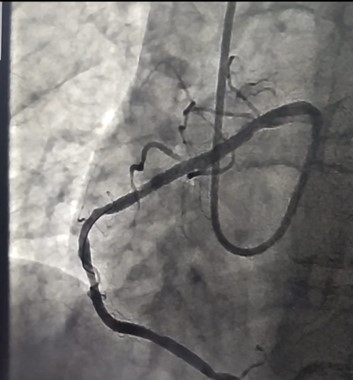

ووقام الفريق الطبى بقسم طب القلب والقسطرة والذي ضم الدكتور مؤمن لطفي مدرس طب القلب والأوعية الدموية والدكتور اسلام راشد مدرس مساعد بقسم القلب بإنقاذ حياة مريضة تبلغ من العمر 40 عاما، تعاني من وجود عيب خلقي في بداية غير طبيعية بالشريان التاجي الأيمن وتم عمل قسطرة علاجية بالتصوير التشخيصي للشريان الأيسر، وأمكن استخدام نفس القسطرة كقسطرة علاجية بعد أن قام الفريق المعالج بإجراء تعديلات لتركيب الدعامة في الشريان الايمن وتم إنقاذ حياة المريضة بنجاح.